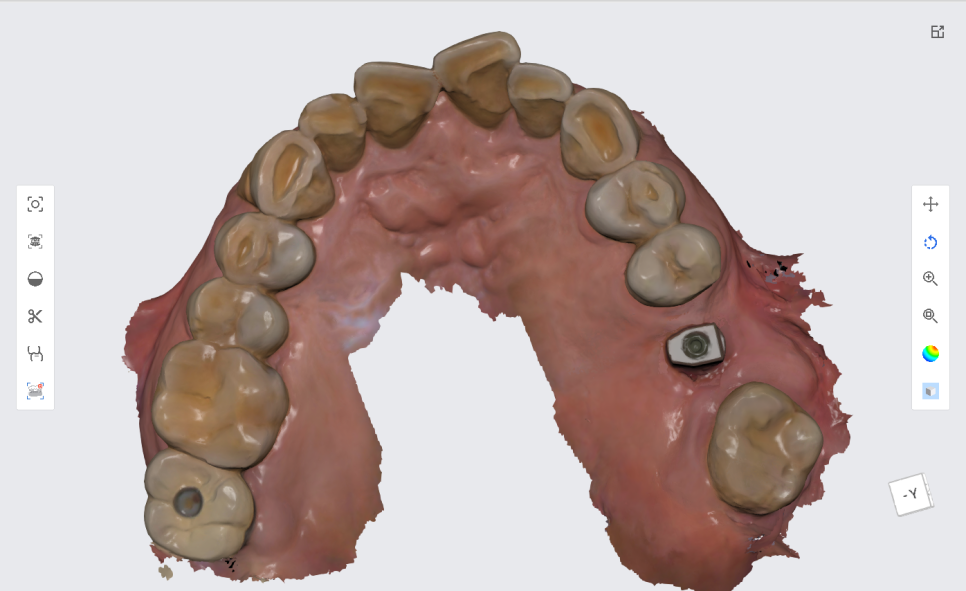

저희 서울바르디치과는 3D 스캐너를 이용하여

본 뜨는 작업을 진행합니다.

컴퓨터 3D 작업을 통해

입안에 찰흙같은 이물질을 넣는 불편감을 최소화하고

더 정교하고 정밀하게 보철 크라운을 제작합니다.

본 뜨는 작업을 진행할 때는

임플란트위에 잠겨져 있던 뚜껑나사를

스캔하는 장치(스캔바디)로 바꾸어서 3D 스캔을 진행 한 다음

다시 원래대로 입안에 있던 뚜껑나사로 연결 해드립니다.